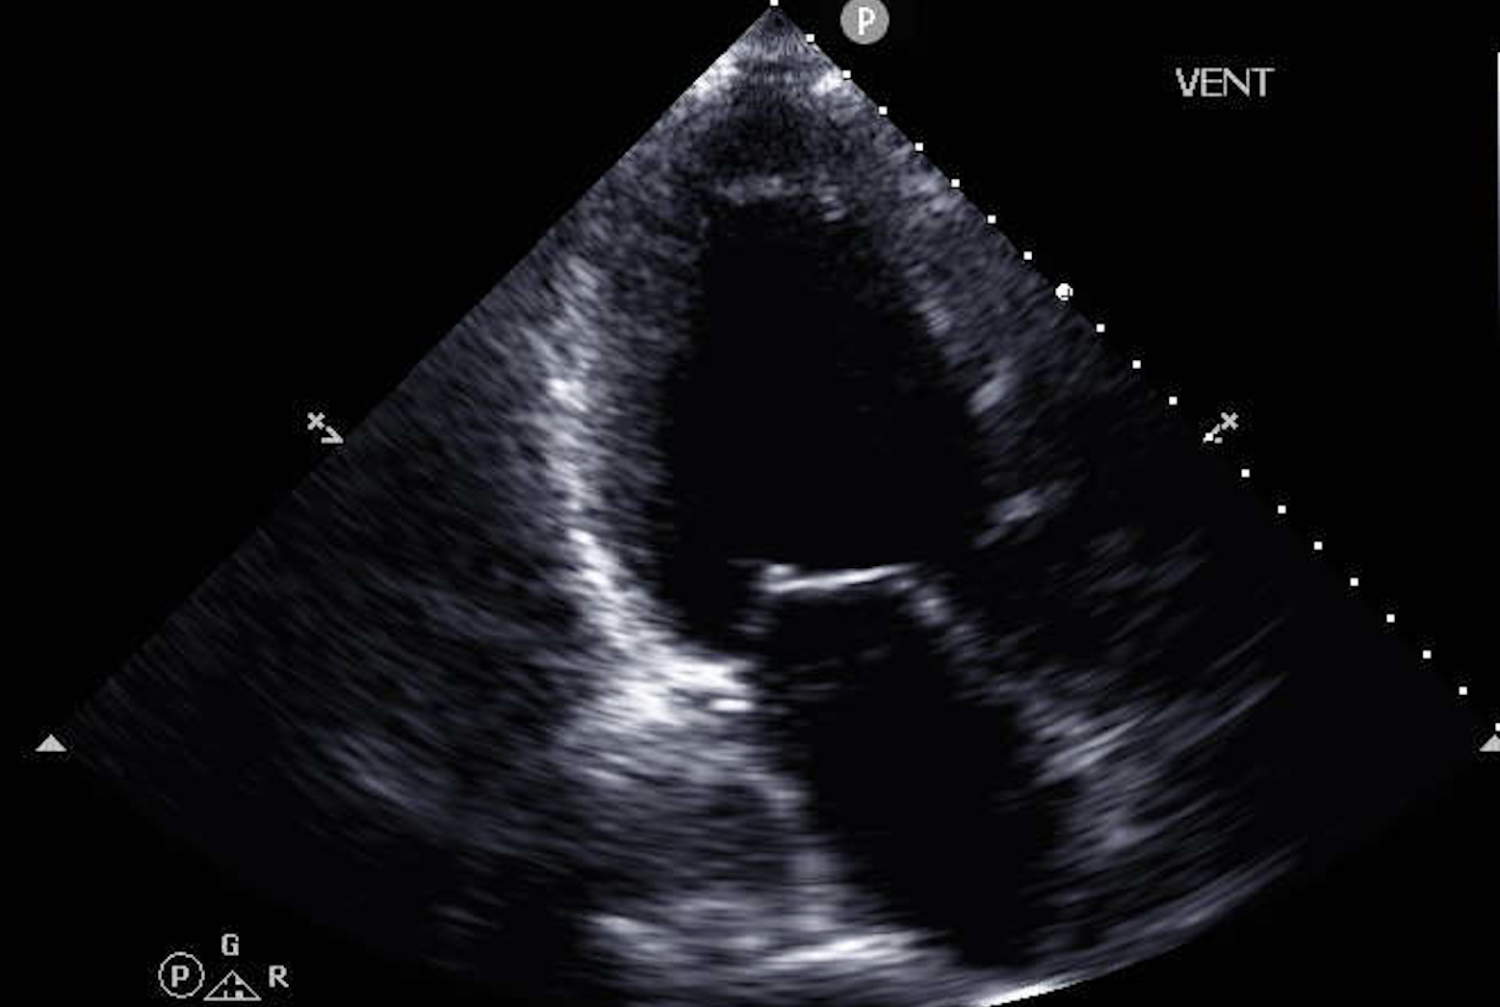

Advanced heart failure is currently detected through cardiopulmonary exercise testing (CPET), which requires specialized equipment and trained staff and is typically only available at large medical centers. Due in part to this diagnostic bottleneck, only a few of the estimated 200,000 people in the United States with advanced heart failure get appropriate care each year. In the new study, published March 3 in npj Digital Medicine, the researchers tested a novel AI-powered method that may remove this bottleneck. The new method predicts with high accuracy the most important CPET measure, peak oxygen consumption (peak VO2), using much more easily obtainable ultrasound images of the patient’s heart plus the patient’s electronic health records.

Using AI on cardiac ultrasound data to help identify advanced heart failure patients seemed one of the most promising applications. Dr. Uriel then approached AI experts at Cornell Tech, Cornell Bowers and Weill Cornell Medicine, who developed the new machine learning model over several years of collaboration.

The AI team led by Dr. Wang, including lead authors Dr. Zhe Huang and Dr. Weishen Pan along with students and faculty at Cornell Bowers, developed a multi-modal, multi-instance machine learning model that can process several distinct data types including ordinary moving ultrasound images of the heart, related waveform imagery displaying heart valve dynamics and blood flow, and various items found in electronic health records.